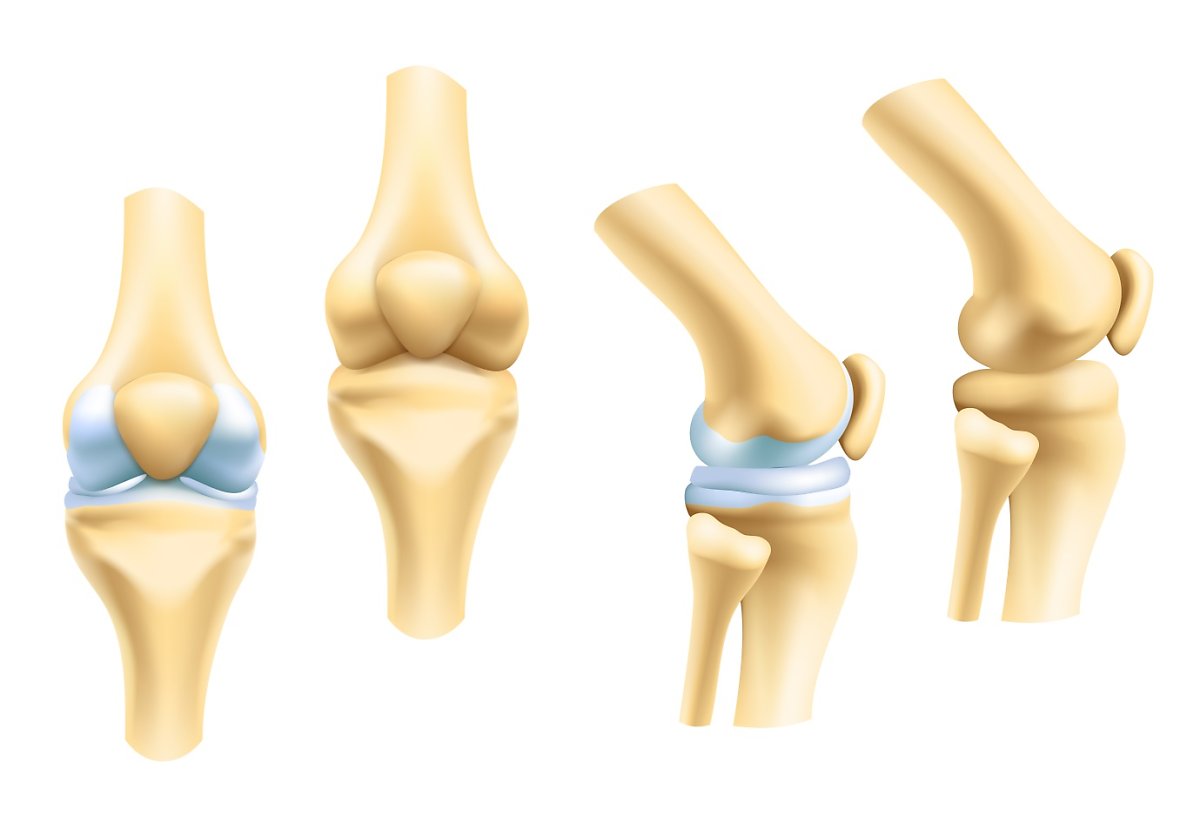

최근 관절 건강과 연관해 국내에서 급격히 인기를 얻고 있는 성분이 있습니다. 바로 콘드로이친입니다. 콘드로이친은 피부, 연골 등의 조직을 구성하는 글리코사미노글리칸의 일종으로, 콘드로이친을 구성하는 당 중 한가지가 황산 에스테르가 된 것을 황산콘드로이친, 또는 콘드로이친황산 이라고 일컫습니다.

표현이 너무 길기 때문인지, 일반적으로 ‘콘드로이친’으로 줄여서 부르는 것을 많이 들을 수 있는데. 콘드로이친과 콘드로이친황산은 유사하지만 다른 성분으로, 식품의약품안전처에서는 관절 및 연골 건강 기능성 원료 콘드로이친의 지표성분을 콘드로이친황산으로 설정하고 있습니다. 즉, 식약처에서 인정하는 유효성분은 콘드로이친황산이라 하는 의미입니다.

콘드로이친황산은 관절과 연골 등에 존재하는 생리활성물질로서 관절 · 연골에 영양을 공급하며 연골 분해 효소를 제한하고 새로운 연골 형성을 촉진하 다고 알려져 있어요 류머티즘학회 유럽연합(EULAR)에서는 2003년에 이미 무릎 골관절염 치료를 위해 콘드로이친황산을 섭취할 것을 강력하게 권고한 바 있어요.

한 번 손상된 무릎 연골은 다시 재생되지 않는다는 특성을 갖고 있고, 노화로 인해 서서히 저하한 체내 콘드로이친은 중년에 이르면 생성할 수 있는 양이 1/20에 불과해요. 콘드로이친은 자연노화로 인해서 관절, 무릎통증, 연골의 노화진행으로 인해 오는 질환에 증상호전을 도와주어 연골세포를 유지시켜주어요. 콘드로이친은 연골세포를 보호해주며 부드럽고 유연하게 유지해서 주어요.

콘드로이친은 연골을 재생 및 복구하고 무릎이 받는 충격과 스트레스를 흡수해서 연골을 보호할 수 있어요. 반대로 콘드로이친이 부족하게되면 연골은 수분 보유력과 탄력을 잃게 되고, 연골이 계속 마모되면서 뼈끼리 마찰을 일으켜 관절염을 유발하기 쉽기 때문인데요.